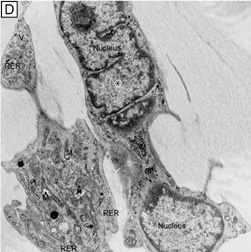

The corneal stroma is maintained by a closed, highly-organized syncytium of keratocytes communicating with each other through gap junctions present on their long dendritic processes.68 Keratocytes occupy 10% to 40% of the stromal volume (decreases from 40% in infancy to 10% in adulthood) that on two-dimensional, cross-sectional views appear as flattened (cell body = 20 μm in length × 1 μm in height), quiescent (i.e., scant intracytoplasmic organelles) cells lying between corneal lamella (Fig. 16A, B). In actuality, keratocytes are three-dimensional, stellate-shaped cells composed of a cell body (≅1 × 15 × 20 μm) with numerous dendritic-processes that extend up to 50 μm in length from the cell body. Two-dimensional tangential sections of the normal cornea suggest that these cells are more highly metabolically active in the resting state than initially presumed; in tangential sections (cell body view = 15 μm width × 20 μm), an abundance of cytoplasmic organelles is commonly seen (Fig. 16C, D).69

Fig. 16. Light and TEM micrographs shown in cross and frontal-sectional views of the cellular corneal stroma demonstrating differences in the appearance of keratocytes depending on the cut, or perspective, of the section. (A) Cross-sectional light microscopy shows that keratocytes are primarily obliquely aligned to corneal surface in the anterior one-third of cellular corneal stroma and are aligned parallel to the corneal surface in the posterior two-thirds. (B) Cross-sectional TEM additionally shows that keratocyte nuclei occupy most of the area of the keratocyte seen in this perspective with only a thin rim of surrounding cytoplasm that contains only small numbers of cytoplasmic organelles. (C) From a tangential perspective, frontal-section light microscopy shows that keratocytes are arranged in a circular fashion. (D) Frontal-section TEM additionally shows that supposedly quiescent keratacytes may be more active in the baseline state than initially thought as an extensive amount of cytoplasmic organelles can be seen in this view. M, mitochondria; RER, rough endoplasmic reticulum; V, vacuoles. *Main portion of nucleus that contains nucleolus. (Modified from Muller LJ, et al. Novel aspects of the ultrastructural organization of human corneal keratocytes. Invest Ophthalmol Vis Sci 36:2557, 1995.)